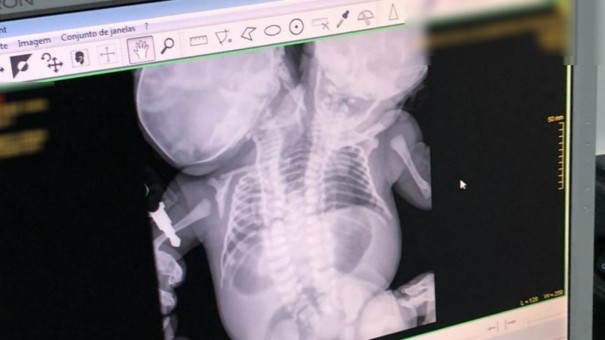

As gêmeas siamesas que estavam internadas no Hospital da Criança e Maternidade (HCM) de Rio Preto (SP) morreram na madrugada desta terça-feira (2). A informação foi confirmada pelo hospital. A causa da morte não foi divulgada.

As gêmeas estavam internadas na Unidade de Terapia Intensiva (UTI) neonatal desde o dia 25 de junho, quando nasceram.

As gêmeas nasceram na Santa Casa de Fernandópolis (SP). Em seguida, foram transferidas para o HCM de Rio Preto.